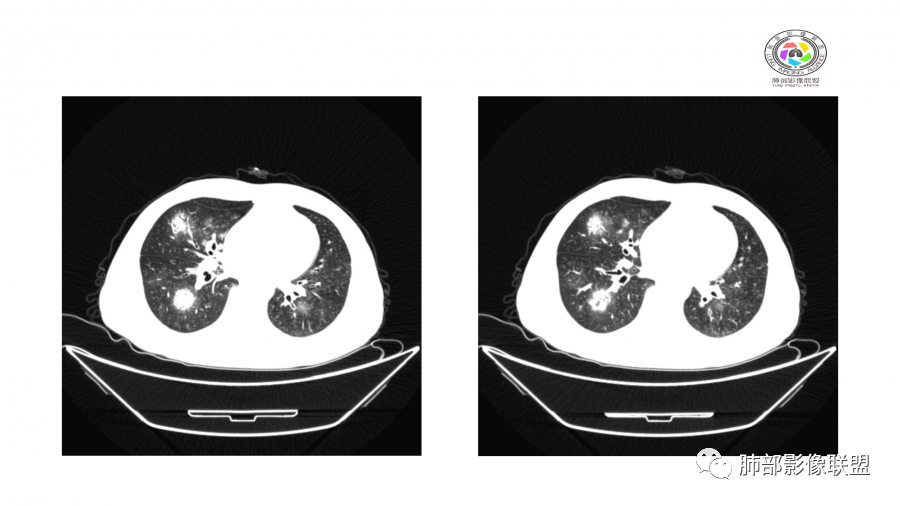

南边:

边界模糊,距离胸膜有间隙,内部支气管通畅

一月后:

病灶此起彼伏